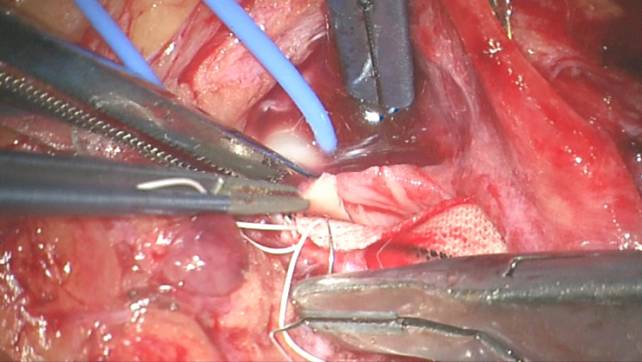

下面的术中照片用来举例说明右侧经内动脉内膜剥脱术的手术步骤:

图21b. 斑块的外侧面已经从颈动脉腔内分离。注意主刀和助手的协同移动。

图21c. 同样,斑块的内壁沿其在颈内动脉和颈总动脉的末端分离后移动。斑块向颈外动脉内的延伸也被分离。